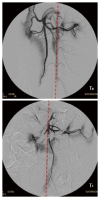

Double balloon enteroscopy (DBE) is an endoscopic technique broadly used to diagnose and treat small bowel diseases. Among the associated complications of the oral DBE, post-procedure pancreatitis has taken the most attention due to its gravity and the thought that it might be associated to the technique itself and anatomical features of the pancreas. However, as the etiology has not been clarified yet, this paper aims to review the published literature and adds new results from a porcine animal model. Biochemical markers, histological sections and the vascular perfusion of the pancreas were monitored in the pig during DBE practice. A reduced perfusion of the pancreas and bowel, the presence of defined hypoxic areas and disseminated necrotic zones were found in the pancreatic tissue of pigs. All these evidences contribute to support a vascular distress as the most likely etiology of the post-DBE pancreatitis.